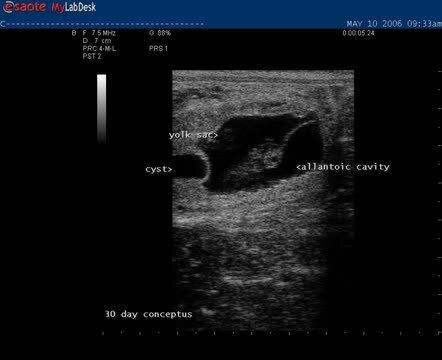

Video Sonogram of 30-Day Conceptus

At 30 days of gestation, the dorsal yolk sac is equal in size to the developing allantoic cavity. A heartbeat should be evident in the embryo proper after 25 days of gestation.

Courtesy of Dr. Patricia Sertich.